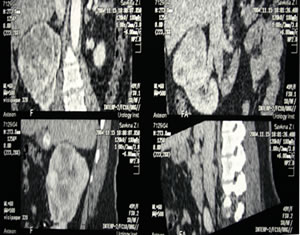

КТ

органов брюшной полости, забрюшинного пространства: |

|